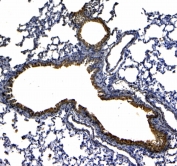

IHC testing of FFPE rat lung tissue with Uteroglobin antibody at 1ug/ml. Required HIER: steam section in pH6 citrate buffer for 20 min and allow to cool prior to testing.